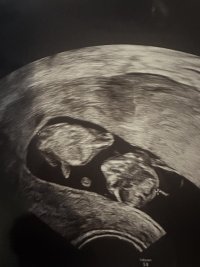

I følge nub-teorien kan det se ut som jente hvis man ser på ultralydbildene mine, tror jeg. Help!

Hvis det er nuben vi ser på bildet så ser det ut som jentenub, men usikker på om det er nuben?